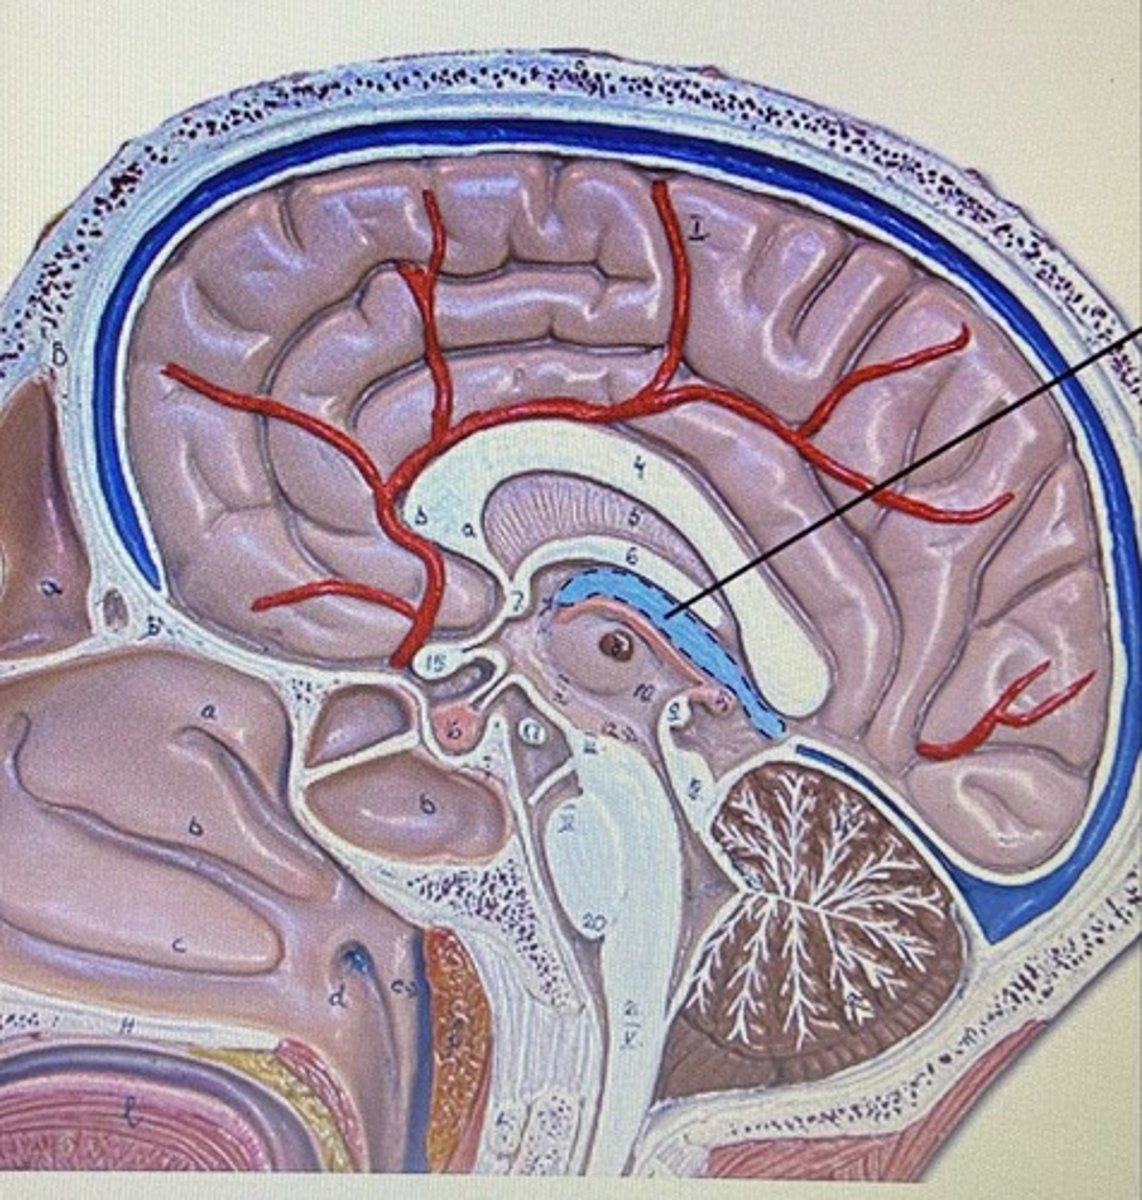

Frontal Lobe

Parietal Lobe

Temporal Lobe

Occipital Lobe

Cerebrum

Cerebellum

Corpus Callosum

Choroid Plexus

Fornix

Thalamus

Hypothalamus

Infundibulum

Pituitary Gland

Lateral Ventricle

Third Ventricle

Fourth Ventricle

Cerebral Aqueduct

Meninges

The three protective membranes

-dura mater

-pia mater

-arachnoid

Dura Mater

Arachnoid Mater

Pia Mater